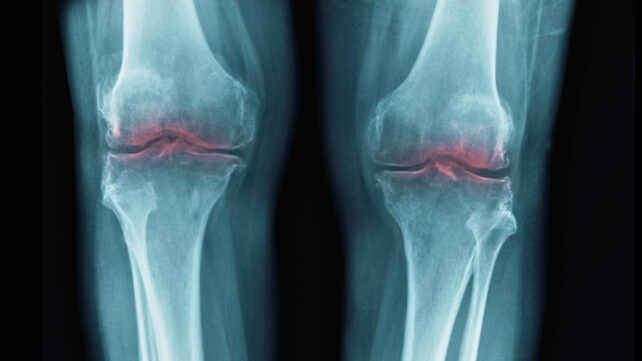

Osteoarthritis is a common degenerative joint disease that causes pain, stiffness, and swelling and reduces your range of motion. It often affects the knees, hips, and hands, although it can also occur in other joints throughout the body.

Using this data, they looked at the effect of exercise on knee, hip, and hand osteoarthritis, and compared it to several alternatives, including doing nothing, placebo (fake) treatments, education, manual therapy, painkillers, injections, and surgery.

Compared to doing nothing and placebos, they found that exercise resulted in small reductions in pain in the hip, knee, and hand: between 6 and 12 points on a 100-point scale.

For knee and hip osteoarthritis, there was evidence that exercise was just as effective at reducing pain and improving function as medicines such as ibuprofen and corticosteroids, which are injected into the joint to reduce inflammation. These also reduced pain by around 5–10%.

The researchers concluded exercise was less effective at improving pain and function than a total joint replacement in people with knee and hip osteoarthritis.